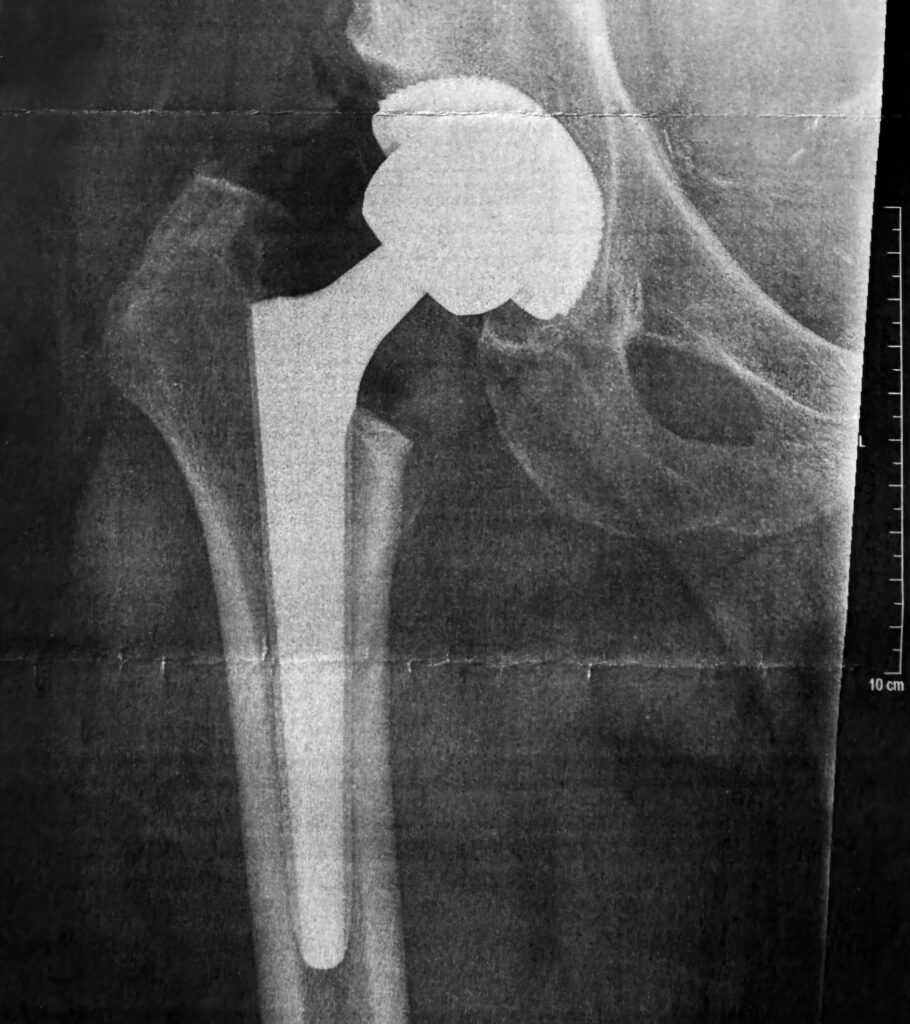

Ende 2025 war es dann soweit. Meine Wahl fiel auf die VITREA Ostseeklinik Damp (ehemals VAMED / Damp 2000). Und wenn ich mir meinen OP-Bericht heute ansehe, weiß ich, dass ich dort in den Händen absoluter Profis war. Denn das war keine „Standard-Hüfte“.

Der Bericht liest sich wie ein handwerklicher Krimi. Die Diagnose lautete: Fortgeschrittene sekundäre Koxarthrose bei Dysplasie und Z. n. Perthes. Auf Deutsch: Mein Gelenk war nicht nur verschlissen, es war durch die Kinderkrankheit auch völlig falsch geformt.

Was die Operateure vorgefunden haben:

- Massive Verformungen: Der Hüftkopf war „komplett entrundet und abgeplattet“, dazu riesige „Osteophyten“ (Knochenwucherungen), die sich über die Jahre gebildet hatten.

- Verkürzte Muskeln: Ein wichtiger Muskel für die Hüftdrehung, der Piriformis, war „komplett verkürzt und teilweise atroph“ (geschrumpft). Er musste während der OP durchtrennt werden, damit das neue Gelenk überhaupt bewegt werden kann.

Trotz dieser extremen Ausgangslage dauerte die OP deutlich weniger als 2 Stunden. Über einen nur ca. 12 cm langen Schnitt wurde mein altes, deformiertes Gelenk entfernt. Es ist faszinierend: Da der Knochenkanal in meinem Oberschenkel sehr eng („zugewachsen“) war, mussten die Chirurgen extrem präzise arbeiten, um den Knochen nicht zu spalten.

Das Hightech-Material in meinem Körper: Eingebaut wurde eine Wagner Conus Prothese (Größe 19) aus Titan, die speziell für solche schwierigen Knochenverhältnisse gemacht ist. Dazu kam eine Allofit IT Pfanne von Zimmer und ein 36mm Keramikkopf. Diese Kombination aus Keramik und modernem Kunststoff (Inlay) verspricht extrem lange Haltbarkeit.